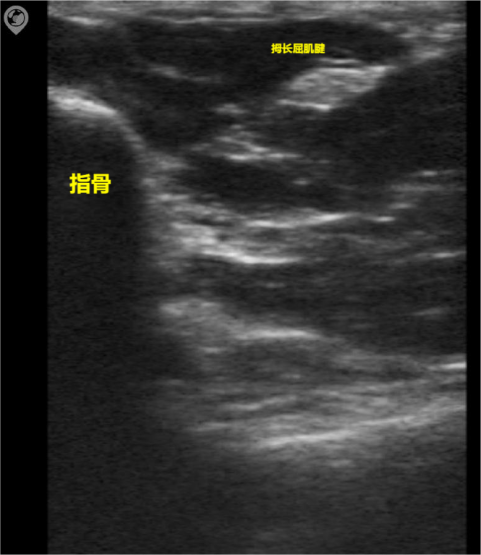

Acoustic shadow

During ultrasonic propagation, strong reflections occur when encountering interfaces with significantly different acoustic impedances, such as stone-water or gas-soft tissue interfaces, resulting in pronounced acoustic attenuation behind these interfaces. This phenomenon is commonly observed behind bones, calculi, and calcified foci.

The image shows the sonogram of the flexor pollicis longus tendon